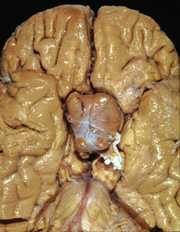

26

A. Low-grade astrocytoma